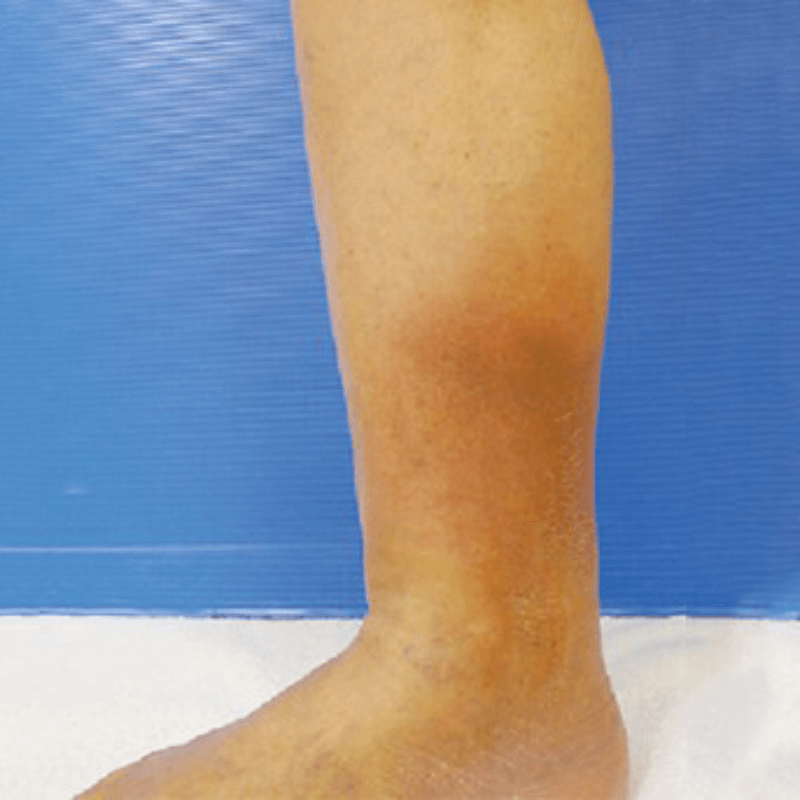

- 静脈の上の圧痛

- 患部に痛みを感じる

- 皮膚の発赤、黒ずみ、炎症など